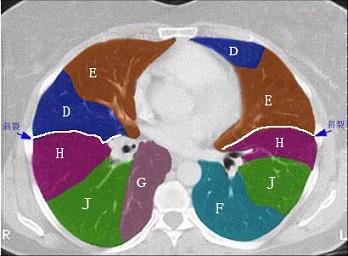

结合肺段模式肺动脉干与右肺动脉层面(见图),选出右肺中叶的组成 ( )A、D+EB、D+E+FC、B+CD、B+C+DE、B

问题 结合肺段模式肺动脉干与右肺动脉层面(见图),选出右肺中叶的组成 ( )

选项 A、D+E B、D+E+F C、B+C D、B+C+D E、B

答案 A